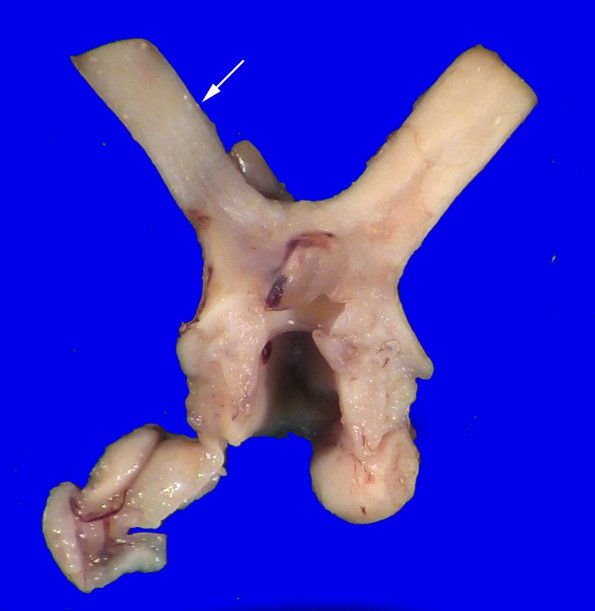

There is left optic nerve (arrow) discoloration, demyelination and atrophy.